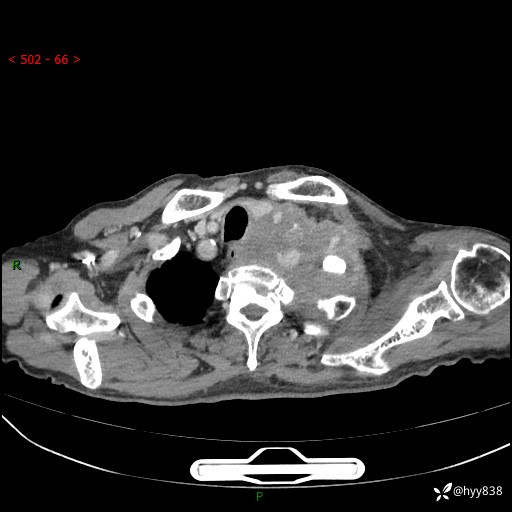

老年男性,气促5月,胸背痛2月。发现肺尖较大肿块,摧枯拉朽之势---结果公布~

现病史:患者于5月前饮酒后突发静息状态下气促不适,无胸闷、胸痛、发热、咳嗽、咳痰等不适,于当地第五人民医院及我院就诊,输液治疗后(具体不详)后气促稍缓解,遂出院后自行口服中草药治疗。近2月出现胸背痛,伴左上肢疼痛、乏力、感觉异常,稍有咳嗽、咳痰,咳黄痰、痰液粘稠,无咳血。为进一步诊治来我院。

胸部CT增强扫描(外院平扫)